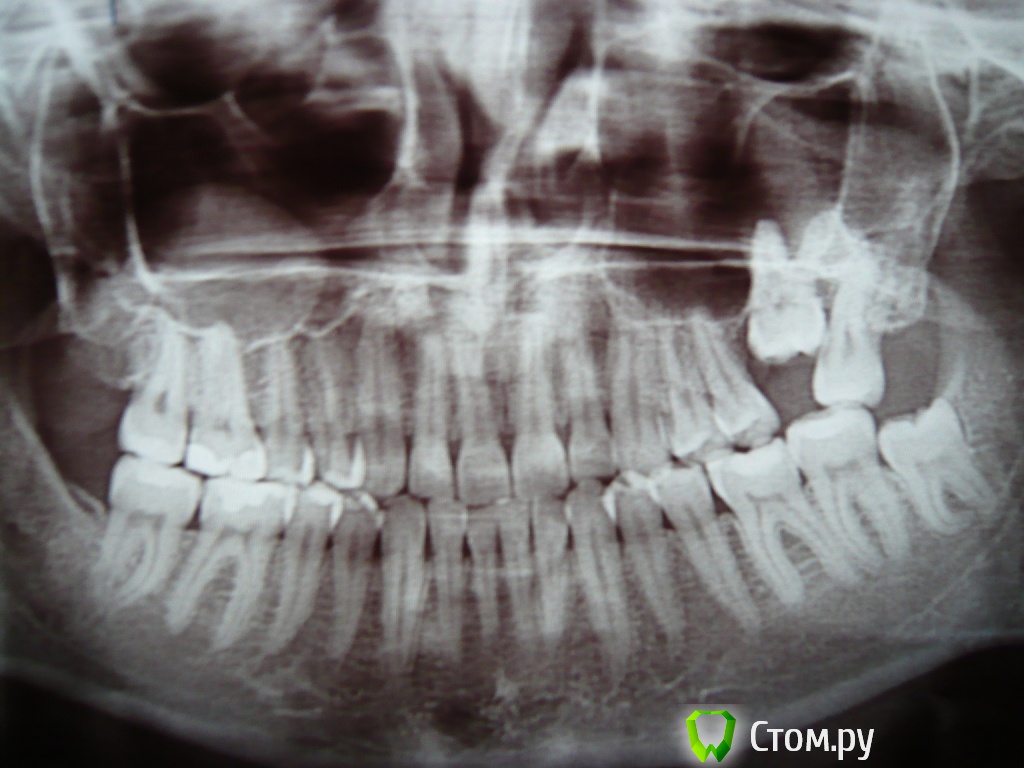

username1 Опубликовано 14 марта, 2014 Поделиться Опубликовано 14 марта, 2014 Доброго времени суток! Мне 23 года. Есть верхняя левая 6-ка, из под десны вылезла на ~ 3 мм. Уважаемые специалисты, прошу ответить на 2 вопроса: 1) целесообразно ли удалить верхнюю левую 7-ку с целью освобождения места для полноценного прорезывания 6-ки? 2) Какова вероятность естественного (без брекет-лечения) полного прорезывания 6-ки? Давно уже мучаюсь с 6-кой и 7-кой, не болят, постепенно появляется налет в области этих зубов, полноценная прочистка затруднительна, неприятный (тухлый) привкус в области этих зубов. Хочу разрешить проблему раз и на всегда. Заранее спасибо. Ссылка на комментарий

IvanK Опубликовано 14 марта, 2014 Поделиться Опубликовано 14 марта, 2014 Обязательно схожу. Больше того, даже предугадываю план лечения. Но хотелось бы услышать альтернативные точки зрения специалистов.Идеальный вариант: кт. Ортодонтическое лечение. http://forum.stom.ru/forum/36-ortodontiia/ http://forum.stom.ru/topic/4655-patcientam/ 2 Ссылка на комментарий